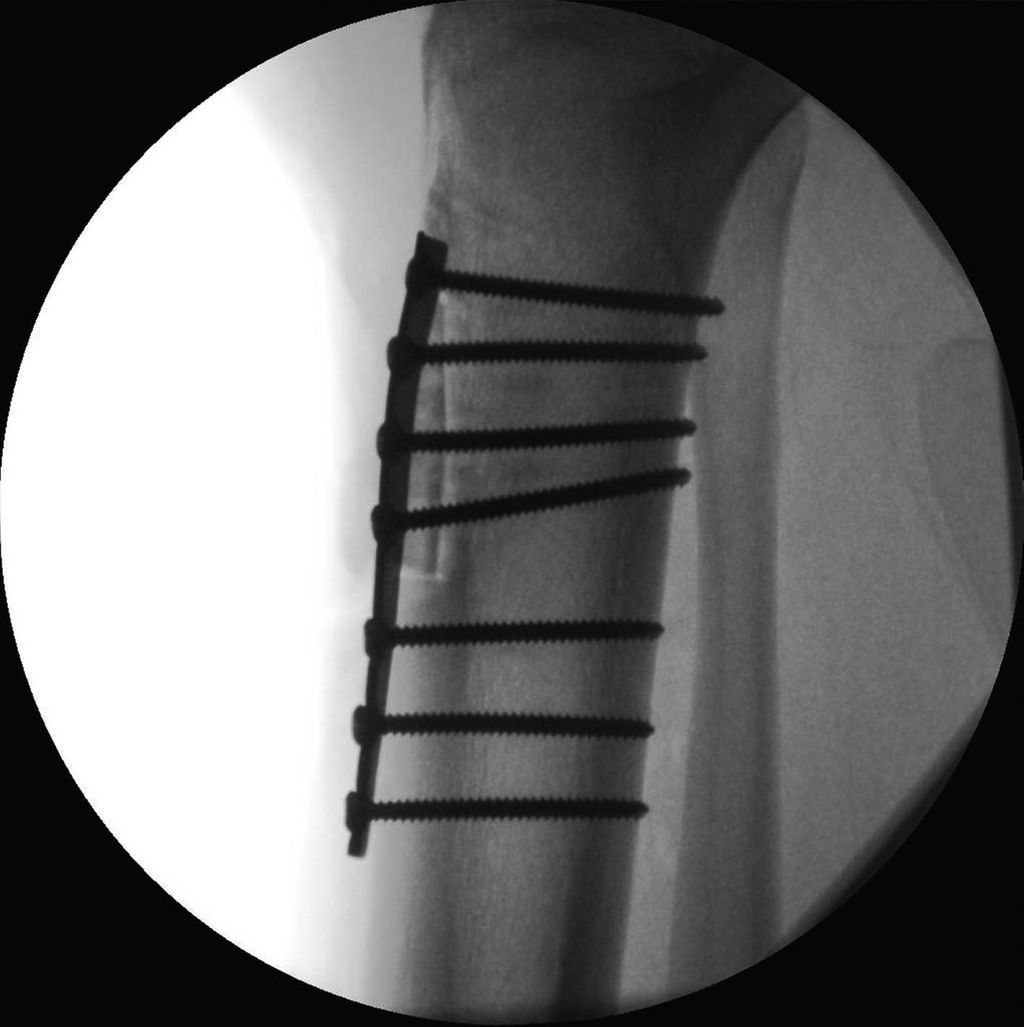

17-jähriger Patient mit wiederkehrenden Patellaluxationen

Aufgrund eines erhöhten Caton-Deschamps-Index von >1,2 erfolgten die Tuberositasdistalisierung und die MPFL-Plastik mit der Gracillissehne (Abb. 2 und 3). Ca. 4 Wochen nach dem operativen Eingriff stürzte der Patient auf das rechte Kniegelenk mit Mehrfragmentbruch des Tuberositasfragments (Abb. 4). Die neuerliche Fixierung erfolgte mittels 3,5mm-Drittelrohrverplattung sowie, wegen des Mehrfragmentbruches im proximalen Bereich, mittels Durchflechtungsnaht und Knochenankern (Abb. 5).